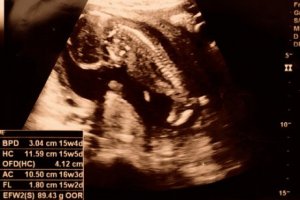

Bazı ultrason görüntülerinde bebeğin cinsiyetini 15. haftada görüntüleyebilmek mümkündür. Bu dönemde fetüsün kolları ve bacakları hızla gelişmeye devam eder ve eklemlerini kullanabilir.

Hamileliğin 15. haftasında bebeğin iskeleti henüz oluşumunu tamamlamamıştır. Fakat omurga oluşumu ve sinir uçları ultrason görüntüsünden ayırt edilebilir. Dahası, fetüs bu dönemde boynunu ve ellerini oynatabilir. Hatta bazı durumlarda bebeği parmaklarını ağzına götürürken görmek mümkündür.